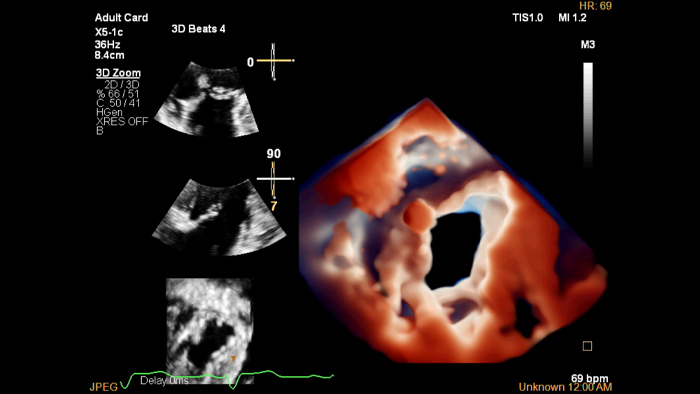

O EPIQ CVX é uma solução de sistemas de ultrassons específica para cardiologia que apresenta avanços significativos em termos de funcionalidade. Ajuda-o a prestar melhores cuidados através de um maior poder de processamento, imagiologia excecional com maior clareza e nitidez e eficiência melhorada dos exames, complementadas pelas capacidades de quantificação comprovadas e robustas do Ultrasound Workspace.